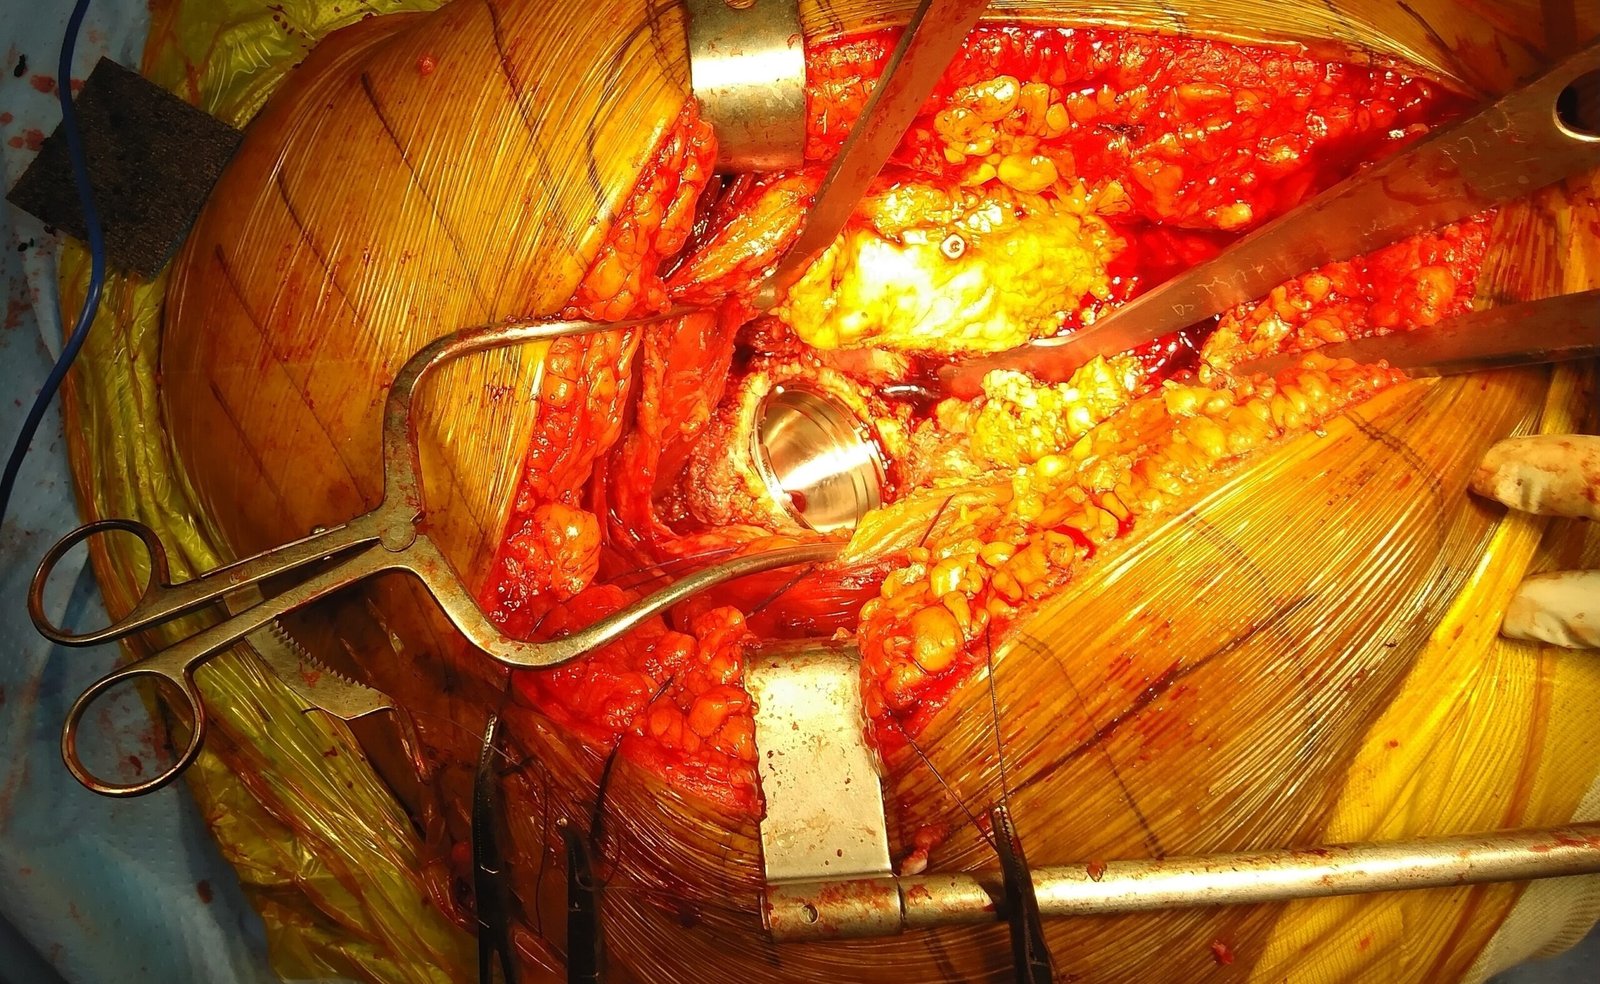

Intra-Op (Photos)